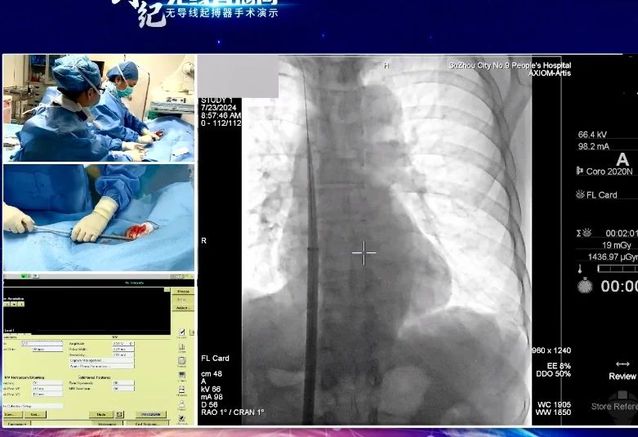

7月24日,“创势纪·无线直播间—苏皖区域无导线起搏器手术演示”在线上举行,金沙娱乐城app 心血管内科主任吴雁鸣参与手术演示,助力提升区域心血管病防治水平。本次活动由江苏省医学会心血管病学分会副主任委员、苏州市心血管病学分会主任委员、苏州大学附属第一医院心内科主任蒋廷波主持,汇聚了一大批专家教授开展手术演示和线上探讨,通过学术交流积极推动苏皖地区心血管病防治水平的进一步提高。

早在2021年,金沙娱乐城app 心血管内科就积极引入和开展无导线心脏起搏器植入术,是我区首家成功独立开展无导线起搏器植入手术的医院。心血管内科主任吴雁鸣是我区首位独立无导线起搏器术者,目前已成功独立植入近30例,受益人群大多为高龄老人,其中年龄最大的患者接受手术时已经103岁。

无导线起搏器,代表心脏起搏领域**技术。无导线起搏器(Micra),俗称胶囊起搏器,是目前世界上最小最轻的起搏器,直径6.7mm,长度25.9mm,重量仅1.75g,是国际前沿的先进起搏技术。虽然小,但其电池续航能力强,工作寿命长达12年,植入后还可以接受1.5T/3.0T核磁共振检查。患者无切口、无伤疤、无凸起、无束缚,几乎感觉不到它的存在,是看不见的起搏器,就像默默守护心律失常患者心脏健康的“隐性保镖”。

这一技术的成熟推广,对区域患者健康有着重要意义。植入心脏起搏器主要针对严重缓慢性心律失常的患者。传统的心脏永久起搏器由脉冲发生器和电极导线组成,医生通过腋静脉或锁骨下静脉将起搏器电极导线送至右心房或右心室,在患者胸前区胸大肌处制作与起搏器大小合适的囊袋,以容纳脉冲发生器。无导线起搏器不同于传统起搏器的地方在于:它不需要使用导线将脉冲发生器连接到起搏电极上。相反,它将脉冲发生器和起搏电极集成在一起,以微缩胶囊的形式直接植入患者的心腔内部。